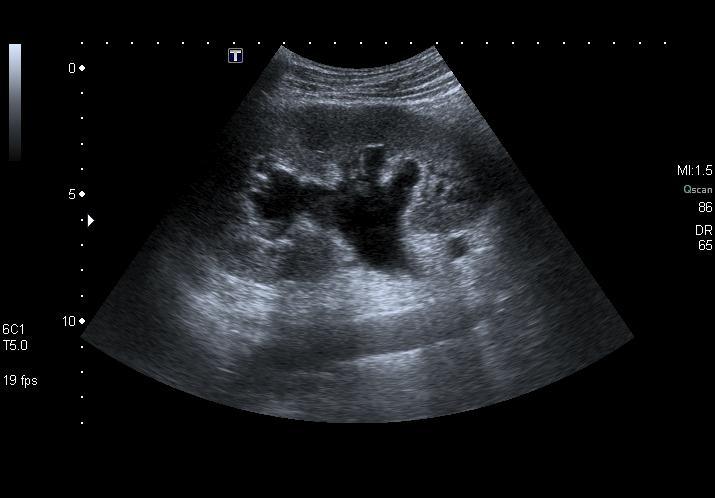

Occlusion : identifier le blocage en urgence.